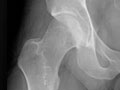

• Encontrar cambios en los huesos causados por afecciones, tales como infección, artritis, crecimientos óseos (tumores) u otras enfermedades de los huesos. Vea imágenes de osteoartritis de la cadera y de osteoartritis de la rodilla.